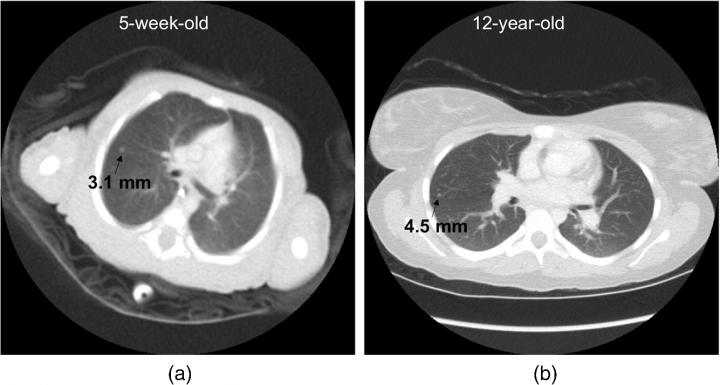

With the wide range of size from newborns to teenagers, size is a particularly dominant factor for pediatric patients in computed tomography imaging of tissues and structures inside the body, note the authors.

The study by Ehsan Samei and Donald Frush of Duke University Medical Center and Xiang Li of the Cleveland Clinic offers a new methodology to determine the interdependency of these data across the range of pediatric sizes. The work is reported in "Size-based quality-informed framework for quantitative optimization of pediatric CT."

Based on two prior foundational studies by the authors, radiation dosage was assessed for organ doses, effective dose, and risk index within nine pediatric age-size groups. The cases, supplemented with added noise and simulated lesions, were assessed in terms of nodule detection accuracy. The resulting continuous accuracy-dose relationships were used to optimize individual scan parameters for each patient category.

The resulting model can be used to optimize individual scan parameters and provide for consistent diagnostic performance across the broad range of body sizes in children, the authors reported. The framework further paves the way for proper optimization of medical imaging exams across pediatric and adult populations, and across varying imaging modalities beyond CT.